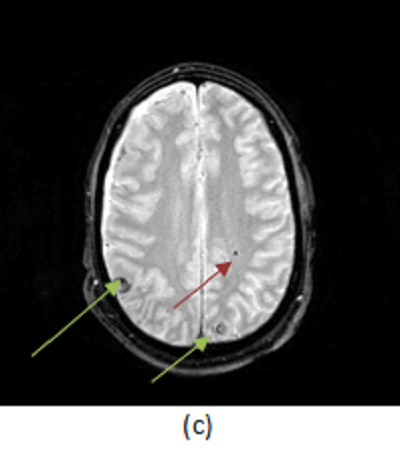

Figure 1: (a, red arrow) non contrast head CT shows a small hemorrhagic contusion in the right parietal lobe. (b, blue arrow) T1 weighted imaging demonstrates two small foci of T1 hyperintense signal consistent with hemorrhage at the grey white junction. (c, green arrow) T2* imaging is most sensitive for blood and intracranial trauma, demonstrating the hemorrhagic contusions identified in (a) and (b) but also a focus of diffuse axonal injury in the left frontal white matter (brown arrow). (Note the hemorrhages are INTRA-axial, not extra-axial as suggested by the answers.)

Initial CT scans may be negative or demonstrate small hemorrhagic contusions. MRI is the gold standard for the evaluation of diffuse axonal injury and demonstrates foci of microscopic hemorrhage in susceptible areas. The appearance of blood on T1 and T2-weighted images depends on its age; these sequences are also less sensitive for the detection of small hemorrhagic foci. As such, susceptibility weighted (SWI) or gradient recalled echo (GRE, T2*) imaging is the preferred method for demonstrating axonal injury. Unlike T1/T2 (spin echo) imaging, SWI and GRE, are sensitive to local inhomogeneity in the magnetic field created by small amounts of blood or calcium – the result is that DAI manifests as a focal loss of signal on SWI or GRE as seen in Figure 1.